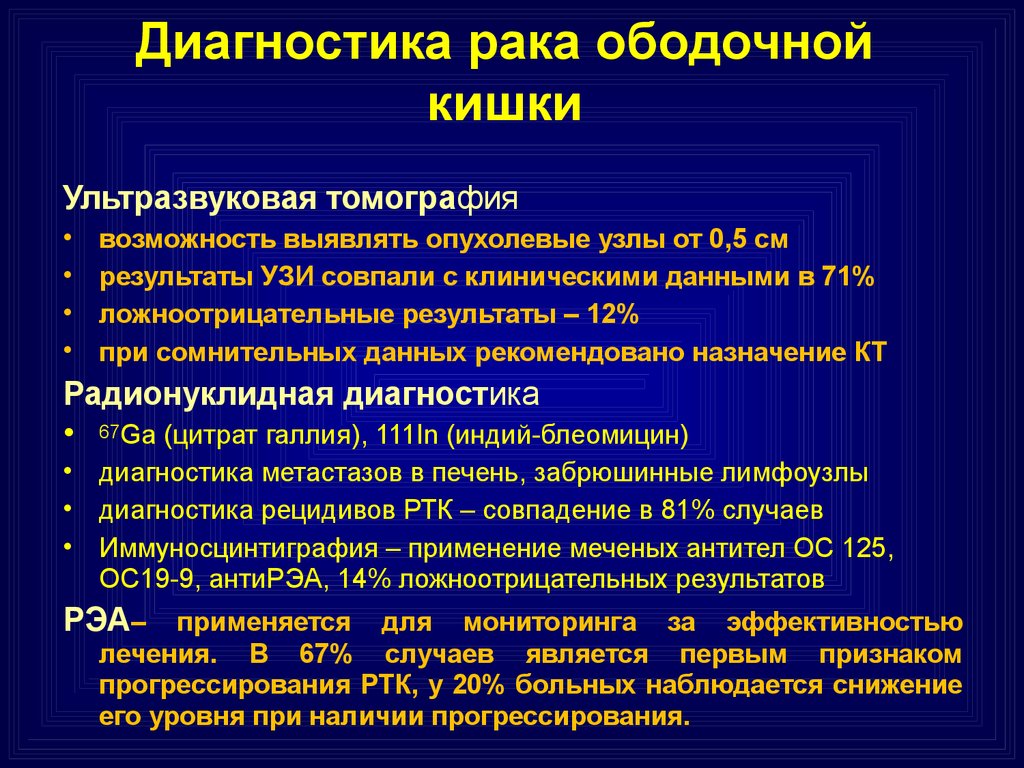

Гиповаскулярные метастазы печени кт. Опухоль желудка метастазирование. План обследования ободочной кишки. Диагноз опухоли ободочной кишки. Диагностические методы исследования ободочной кишки. Алгоритмы диагностики заболеваний толстой кишки.

План обследования ободочной кишки. Диагноз опухоли ободочной кишки. Диагностические методы исследования ободочной кишки. Алгоритмы диагностики заболеваний толстой кишки. Петрокливальная менингиома. Менингиома доброкачественная.